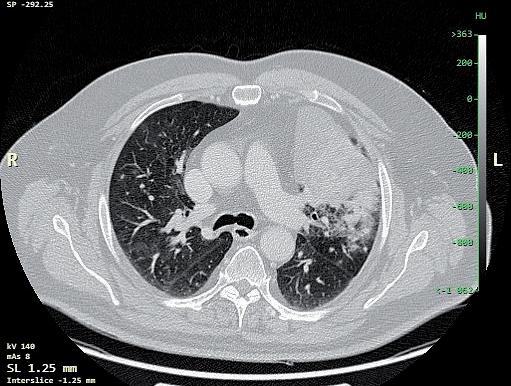

obr. 3.7 Metabolicky aktivní nádor periferně subpleurálně na konvexitě a při interlobiu dolního laloku vlevo (přechod S6 a S9) na CT (a) a PET CT (b) obraze je příkladem ideálního ložiska pro videotorakoskopickou excizionální biopsii klínovitým vytětím pomocí stapleru. Byl prokázán adenokarcinom. Po dolní lobektomii bylo patologem v parenchymu nalezeno ještě satelitní nádorové ložisko, které bylo pod detekčními možnostmi současných parakli nických vyšetřovacích metod

Na tomto místě je potřeba z praxe uvést, že výraz nou pomocí pro předoperační posouzení, jestli je nádor plíce zhoubný nebo nezhoubný, nemusí být ani PET CT [35, 36], které je v dnešní době jinak zásadním vyšet řením (obr. 3.11). Nevelké metabolicky aktivní ložisko i s aktivitou spádových uzlin může být počínající plicní malignitou, ale také zánětlivým procesem (obr. 3.12). Objemnější, asymptomatický, náhodně objevený, cent rálně v laloku umístěný nádor s výraznou metabolickou aktivitou, včetně nepravidelné metabolické aktivity uz lin u uhlokopa, může být jen koniotickým uzlem (obr. 3.13). Naopak jako neaktivní nemusí být zobrazeny pouze zhoubné nádory pod aktuálním kritickým roz lišovacím objemem pro PET CT (průměr léze 8 mm).